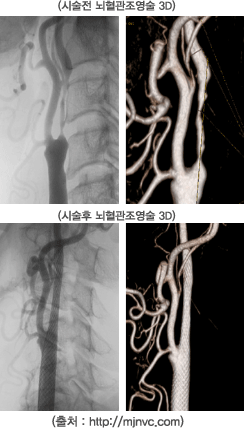

• - 경관혈관성형술(Transluminal angiography)과 스텐트 삽입술(Stent insertion)이 있으며 뇌에 혈액을 공급하는 혈관이 심하게 좁아져 있는 경우 시술이나 혈관조영술을 이용한 치료방법입니다. 풍선확장술 등을 통하여 좁아진 혈관을 넓혀준 후 스텐트라는 장치를 넣어서 다시 좁아지는 것을 방지하는 시술로 뇌경색의 발생 또는 재발을 줄여줄 수 있습니다.

출혈성 뇌졸중에서 동맥류성 지주막하 출혈은 대부분 큰 동맥에 생긴 꽈리 모양의 동맥류가 터지기 때문에 뇌혈관조영술로 동맥류의 위치와 혈관상태를 확인한 후 동맥류 결찰술(clipping)이나 코일색전술(coil embolization)을 통해 동맥류를 없앨 수 있습니다.